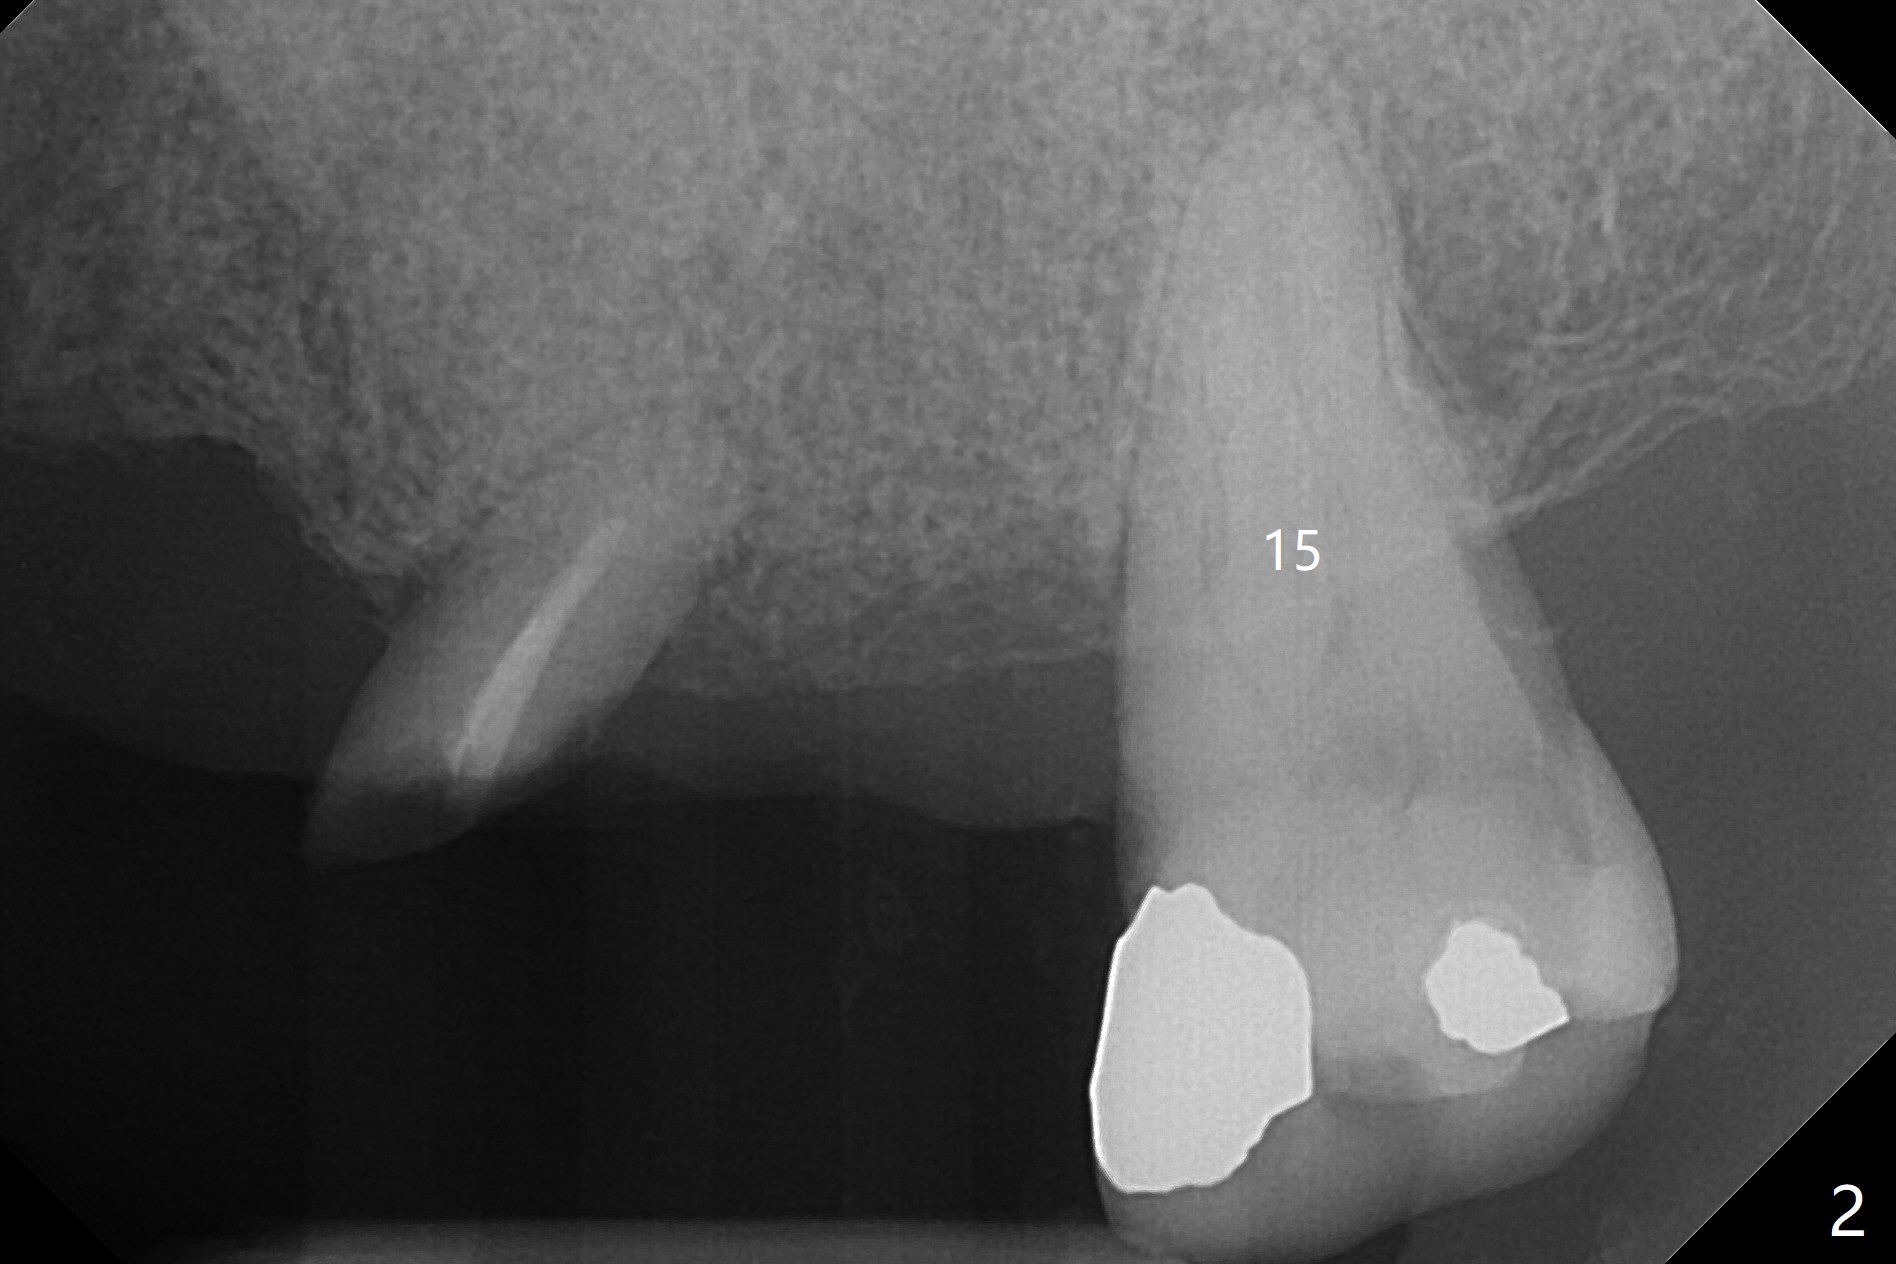

A 70-year-old man has poor dentition, needing extraction for dentures (including #2 and 3 in Fig.1). To save the abutment tooth #1 (with severe bone loss) for RPD and to stop hemorrhage, allograft and Osteogen Plug are placed at #2 and Collagen Plug at #3. Five-O PGA sutures remain in place 9 days postop (Fig.3).